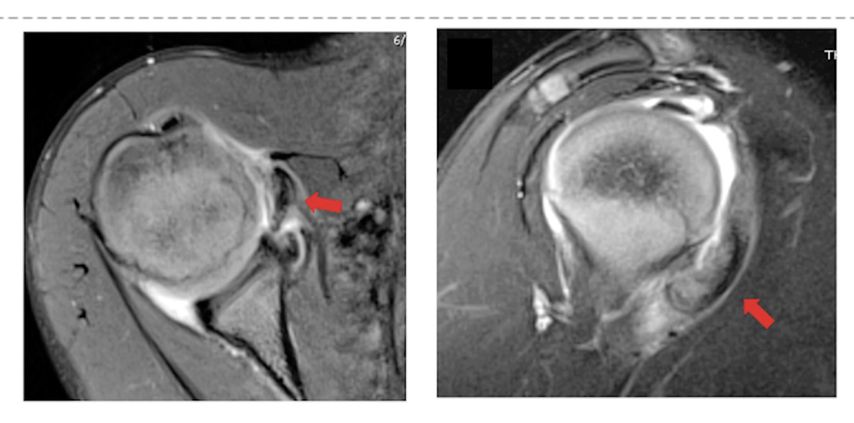

Auch im Kindesalter kann es Rupturen der Rotatorenmanschette geben, oft sind dies aber osteochondrale Übergangsfrakturen beziehungsweise Avulsionen. Je höher der knorpelige Anteil, desto eher wird das Problem auf dem nativen Röntgen übersehen und erst im MRI sichtbar. Daher macht ein solches bei anhaltenden Beschwerden und Dysfunktion (>3 Wochen) nach einem Sturz auch Sinn. Bei der positiven Diagnose ist eine Manschettennaht indiziert, diese muss aber unter Beachtung der Wachstumsfuge und des typischerweise sehr weichen Knochens im Humeruskopf des Kindes durchgeführt werden (Abb. 6).

Abb. 6: Avulsion des Subscapularis inklusive des cartilaginären Tuberculum minus (rote Pfeile)